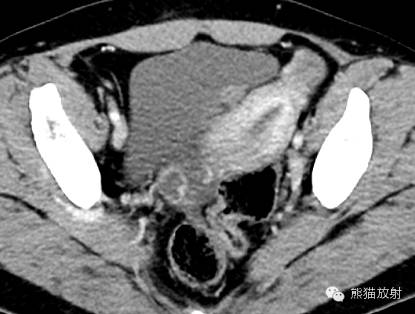

女,33岁,2年余前在月经期时,出现尿频、尿急,伴全程肉眼血尿,呈淡红色,无血块,有时可有尿痛;经期结束后,上述症状消失。

膀胱镜检查:膀胱三角区及各壁粘膜可见充血炎性改变,三角区后方可见一范围约1.5×2cm的粘膜隆起,局部可见紫蓝色的粘膜下瘀斑,于该处取病理2;

活检病理示:(膀胱)送检少许组织被覆尿路上皮,呈轻度慢性炎,间质中查见少数散在的腺体,结合临床和免疫表型,符合子宫内膜异位;免疫组化:ER 、PR 、CD10-、CK34βE12±、CK7±。

膀胱子宫内膜异位症

膀胱内异症 病理图(来自文献)

诸病灶分别如下图中圆圈所示: